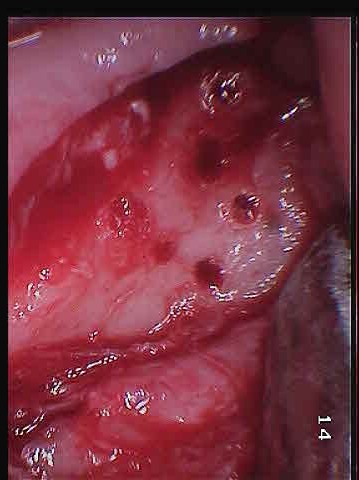

I showed these to my dentist and he agreed to operate on me as soon as possible. Since I had seem him last he had invested in a new FLIR (forward looking infrared) camera. He took some photos of my face with them before the surgery and you could actually see a hot spot on my jawline where the infection was. Unfortunately at this time I don't have these photos. That together with the MRI was all the information he needed to operate. The MRI had shown that basically the entire area was infected. In the previous surgery he had simply not opened up enough of the bone to get at all the infection. This time they cut the entire top of the bone off to reveal the defect. Here are some photos of the surgery. The first if with the gum retracted, the holes in the bone are from infection, not made by the dentist. He described my jawbone as looking like swiss cheese. The second is with the entire top cut off. You can see there is a large defect in the bone.